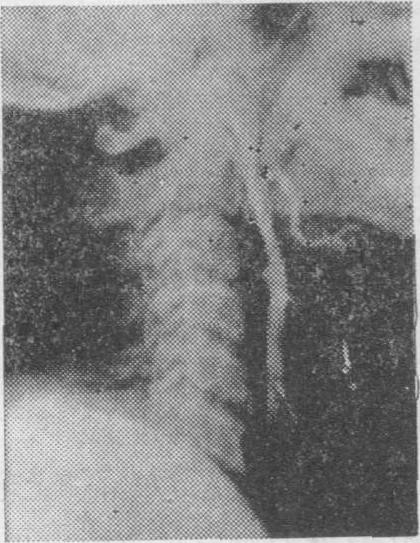

❷锁骨下动脉盗血综合征 (subclavian arterysteal syndrome) 典型的是锁骨下动脉在椎动脉分出之前发生阻塞或狭窄 (图2),病变侧手臂活动时血液自椎-基底动脉反流入上肢而出现椎-基底动脉供血不足的症状,检查见病变侧桡动脉脉搏迟缓,锁骨下动脉处有杂音,两上肢血压相差20mmHg。

图2 锁骨下动脉盗血综合征